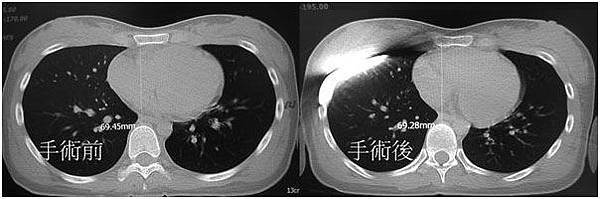

一年多前, 曾來我門診, 經檢查有明顯廣泛型凹胸併有心肺壓迫, 胸骨至脊椎間距只有6.9公分, 最近又來門診, 已經在他院做過手術, 但仍明顯呼吸矯促, 再做檢Dr. 朱志純 發表在 痞客邦 留言(0) 人氣(770)